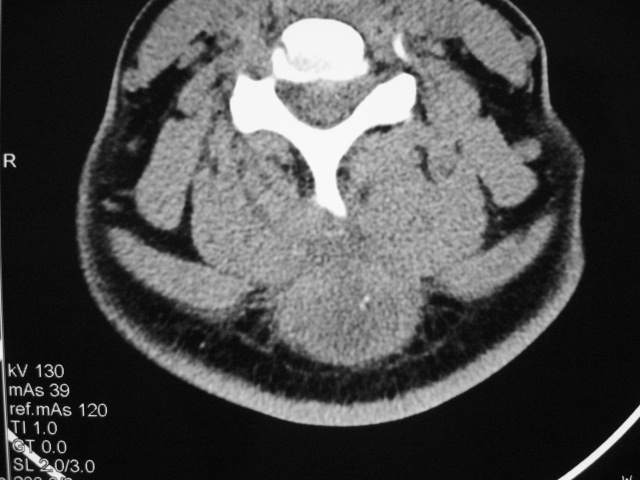

女,46岁,发现颈后区肿块3月余.

颈后软组织肿块,内可见坏死区及点状钙化,邻近颈椎棘突可见破坏,邻近肌间隙模糊,肿块周围脂肪间隙可见索条状影。

考虑:1)感染,结核可能;

2)肿瘤不能排除。